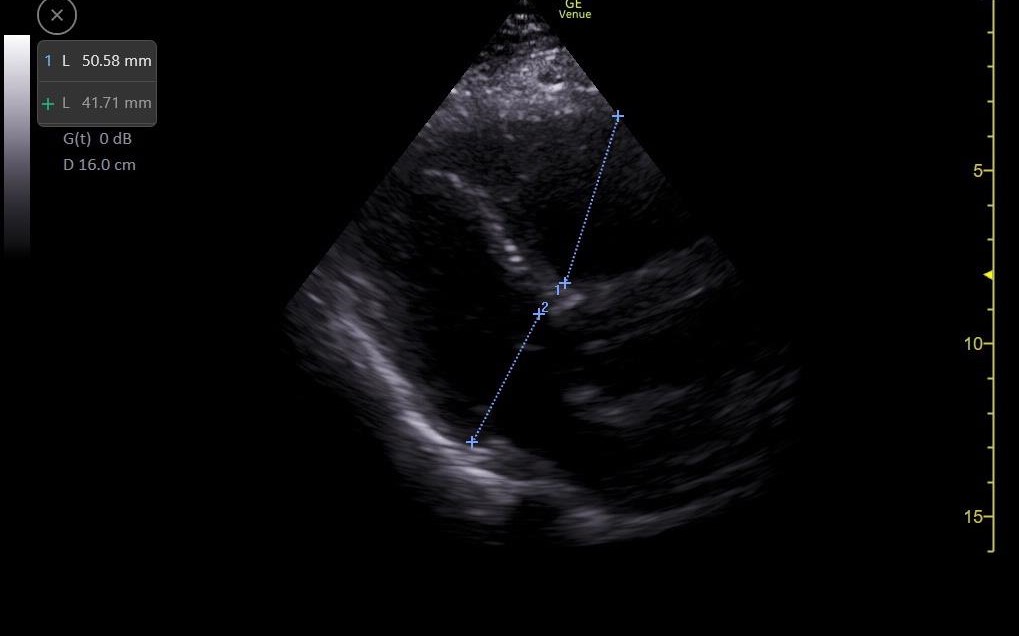

Se realiza ecografía clínica de vasos en miembros inferiores objetivándose un trombo en vena poplítea derecha y ecocardioscopia con dilatación de ventrículo derecho.

Solicitamos electrocardiograma donde se objetiva taquicardia sinusal a 105 lpm y ondas T negativas en V1 y V2, radiografía de tórax sin alteraciones y analítica sanguínea donde destaca DD 156223. Se completa el estudio realizándose angioTC de arterias pulmonares que es informado como tromboembolismo pulmonar bilateral con afectación de todas las ramas lobares bilaterales con imagen compatible con infarto pulmonar en lóbulo superior izquierdo y signos de sobrecarga cardíaca derecha.

Tromboembolismo pulmonar con sobrecarga de cavidades derechas.